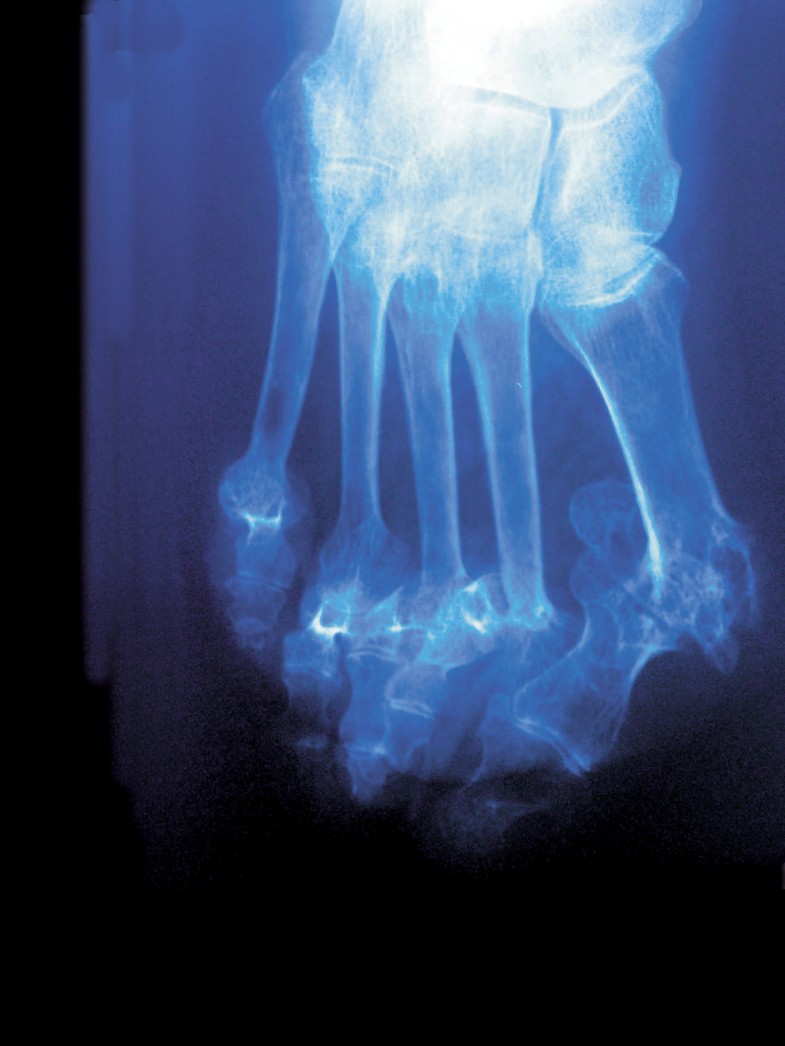

Früher Gang und Gäbe, heute Ausnahmeerscheinungen: durch Rheuma schwer deformierte und zerstörte Gelenke, hier am Fuß.

© Klaus Rose